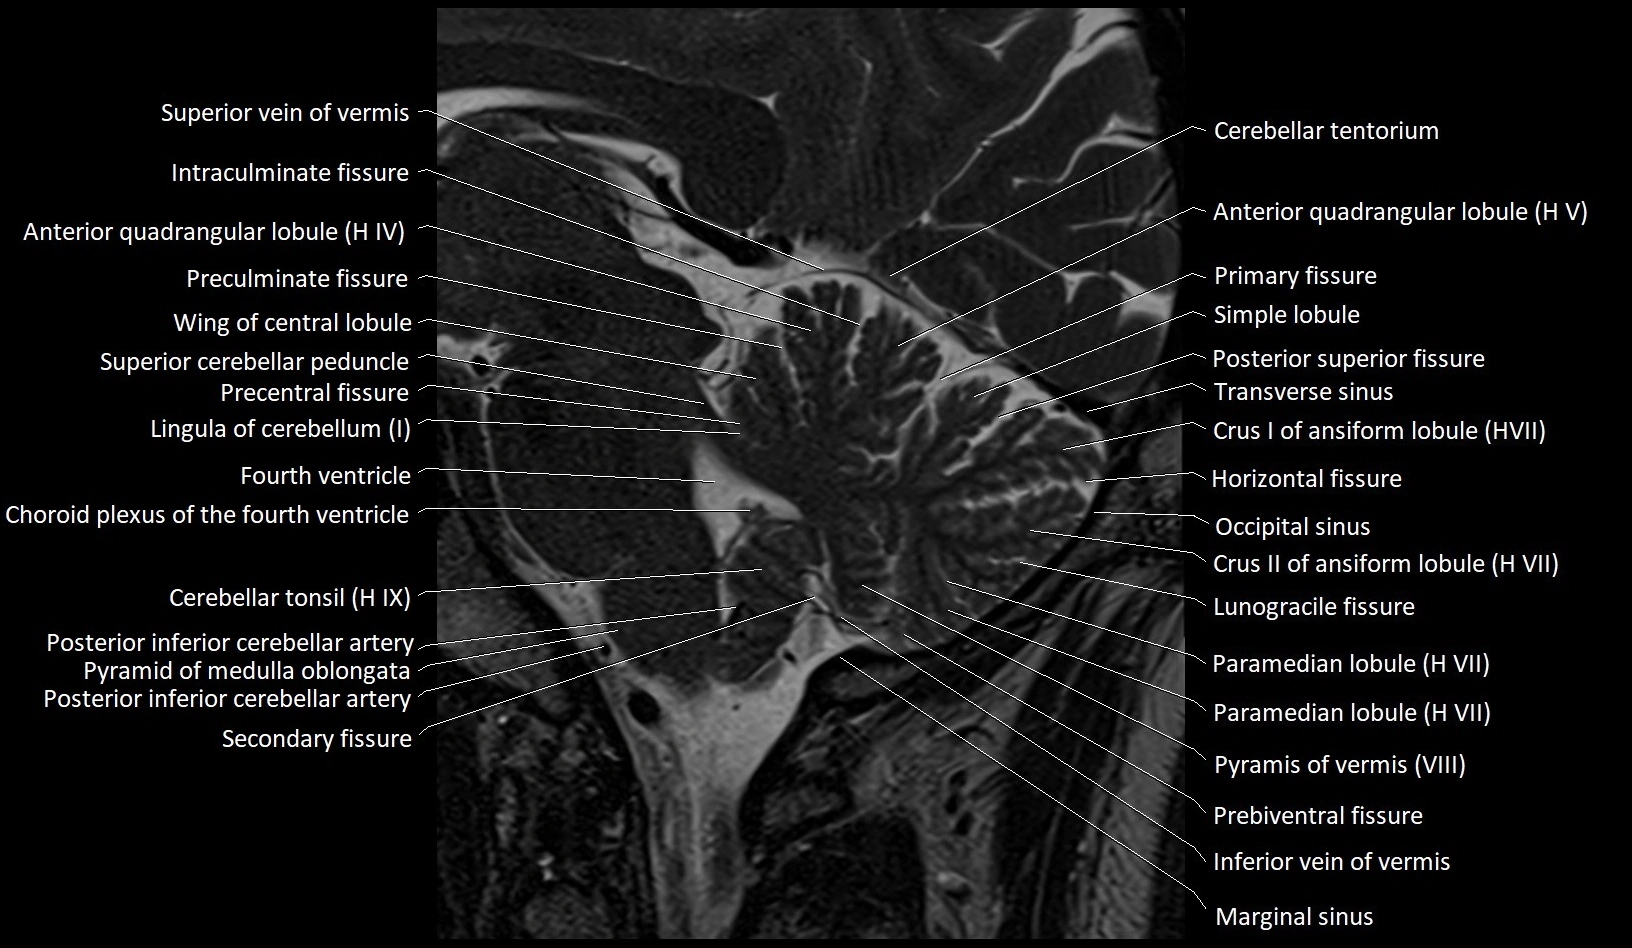

MRI images